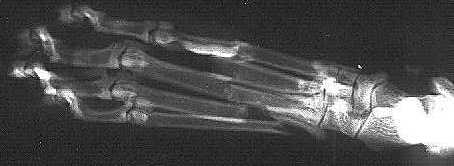

When we left for work in the morning, she was fine. When we came home, she was limping around with a floppy foot. Mary took Maggie to the kitty emergency room. The x-rays confirmed our worst fears: Maggie had broken all four metatarsal of her right hind paw. Ignore her little toes all scrunched up at the left of this x-ray and focus on the middle where the bones don't line up anymore. |